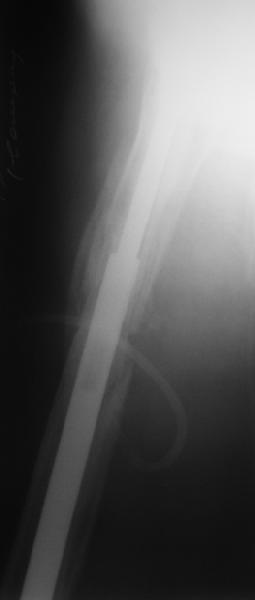

Reminded me of a case I did a couple years ago - 30 year old woman with juvenile rheumatoid arthritis and a nonunion below her stem. Fixed with retrograde nail which docked with the stem and a lateral locking plate. Image attached. One of the companies should come up with a stem design and nail system that anticipates this need.